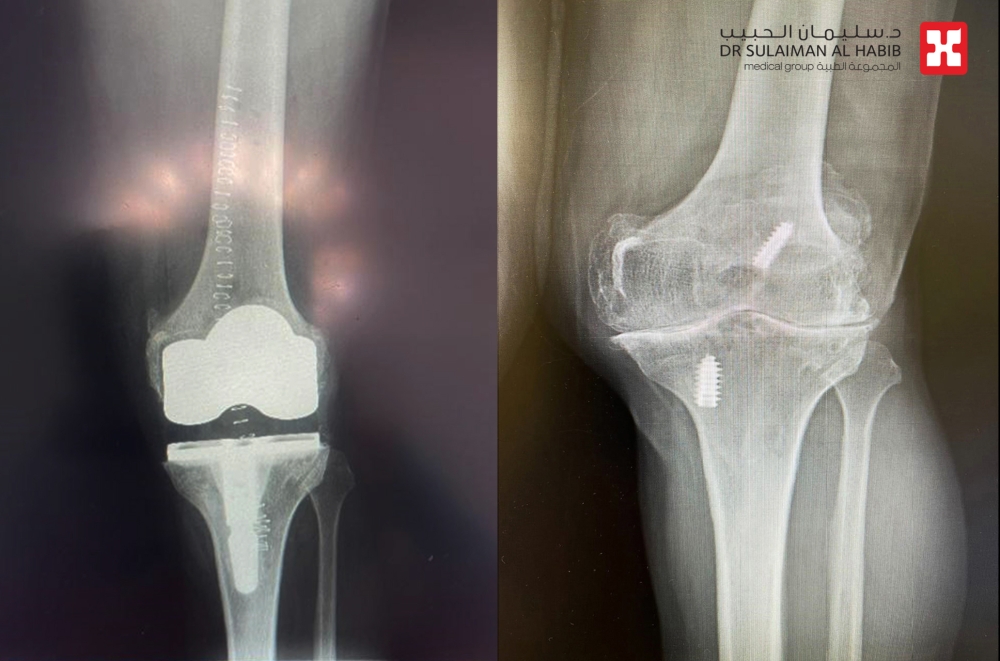

عند وصول المراجعة إلى العيادة، خضعت لتقييم شامل ودقيق بدأ بالاستماع إلى الشكوى المرضية بشكل تفصيلي، ثم الاطلاع على تاريخها الطبي الكامل. بعد ذلك، تم إخضاعها لسلسلة من الفحوصات الطبية المتقدمة، شملت الأشعة السينية الرقمية على جميع اتجاهات مفصل الركبة، إضافة إلى تحاليل مخبرية متكاملة.

وأظهرت النتائج وجود خشونة شديدة من الدرجة الرابعة، وهي أعلى درجات تآكل المفصل، مع احتكاك مباشر في العظام، وتآكل بالغضاريف المحيطة بالركبة، وتكوّن تكلسات خلف المفصل، فضلًا عن وجود انحراف وتقوّس واضح في شكل الركبة. هذه المعطيات أكدت أن العلاج التحفظي لم يعد مجديًا، وأن التدخل الجراحي أصبح الخيار الأنسب لاستعادة الحركة وتخفيف الألم.

كما تم خلال العملية تصحيح الانحراف والتقوس في الركبة باستخدام دعامة متطورة تشمل الساق والفخذ، ما أسهم في استعادة المحور الطبيعي للطرف السفلي وتحقيق توازن أفضل أثناء المشي.